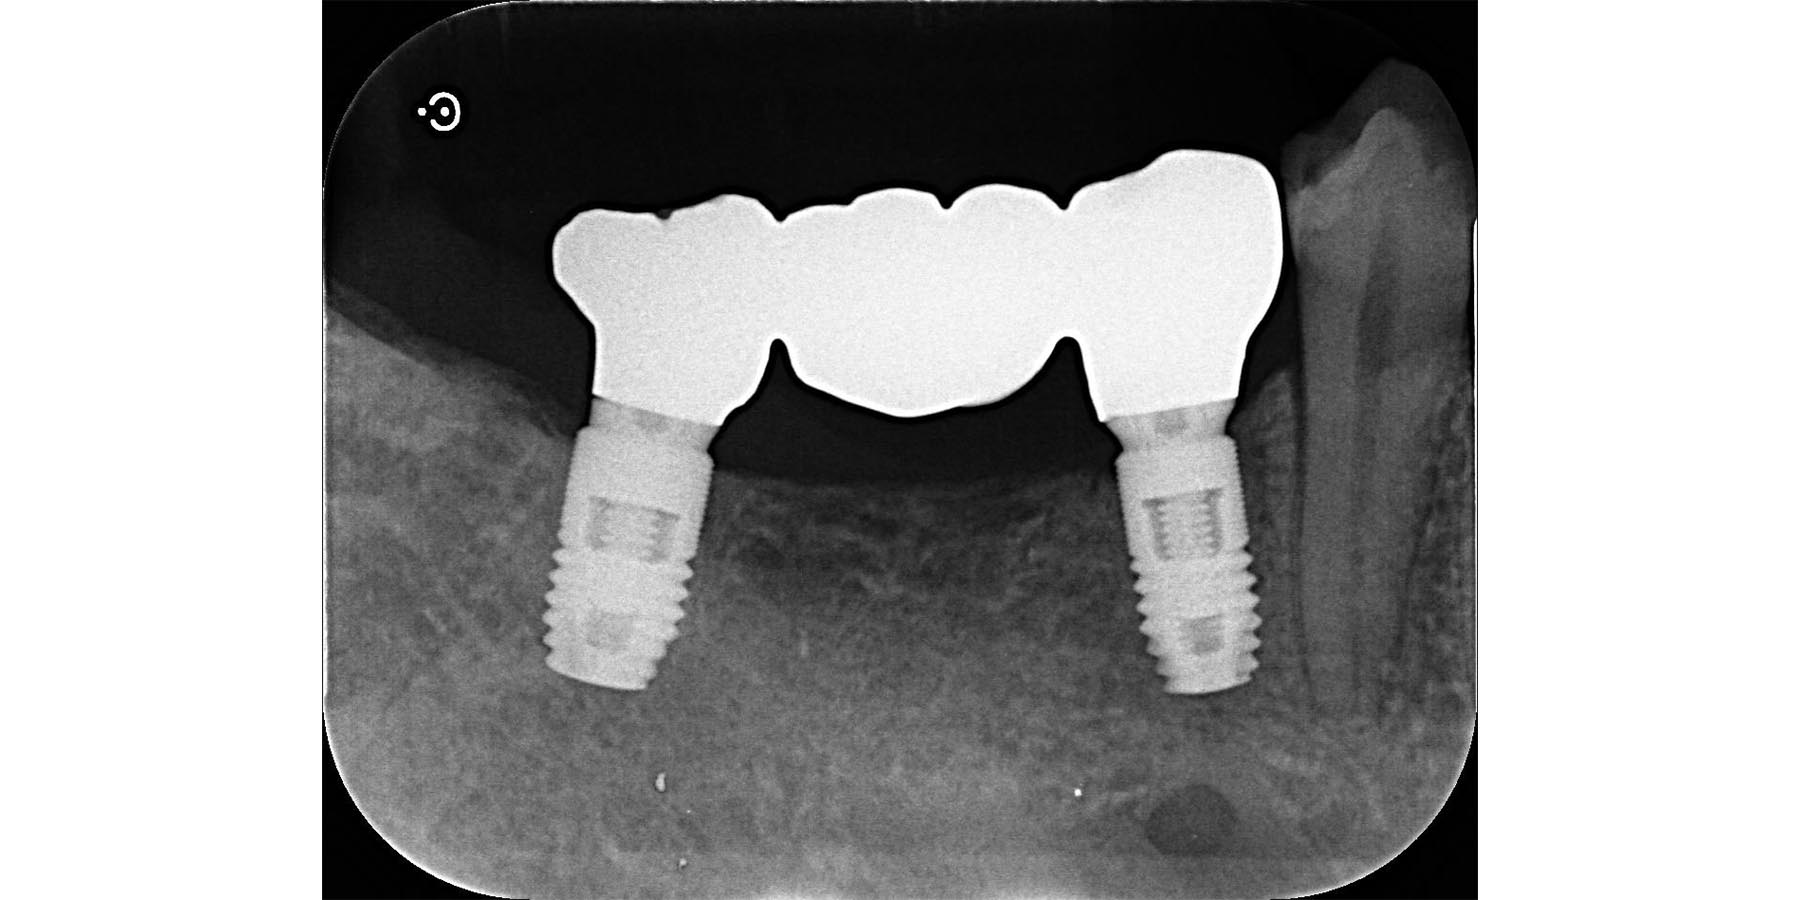

インプラント埋入後

被せ物セット完了

| 治療内容 | 左下5.7右下6のインプラント治療(3本) |